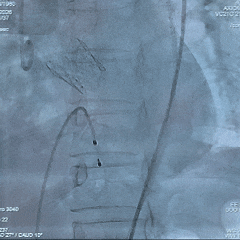

术中影像

根部造影

瓣叶活动差,可见明显反流,猪尾导管测量跨瓣压差约50mmHg

20mm球囊预扩

微腰微漏,左右冠均显影

造影确认瓣环与瓣膜位置

瓣膜0位初始定位释放,展开过程微微下移

全展开位造影评估

瓣膜呈直筒型,微腰,大弯侧约瓣下3mm,少量反流,冠脉显影

瓣膜无张力脱钩

植入后造影评估

瓣膜位置合适,可见少量反流

多角度造影评估

瓣膜形态可,冠脉显影,猪尾测量压差为0